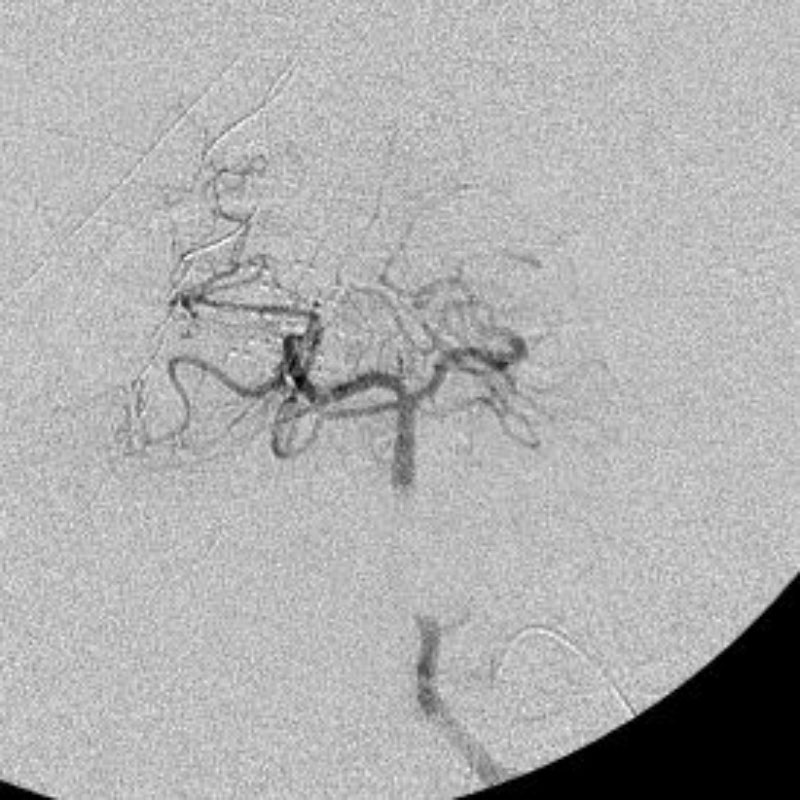

脳血管撮影

手術前

手術後

手術中

手術写真